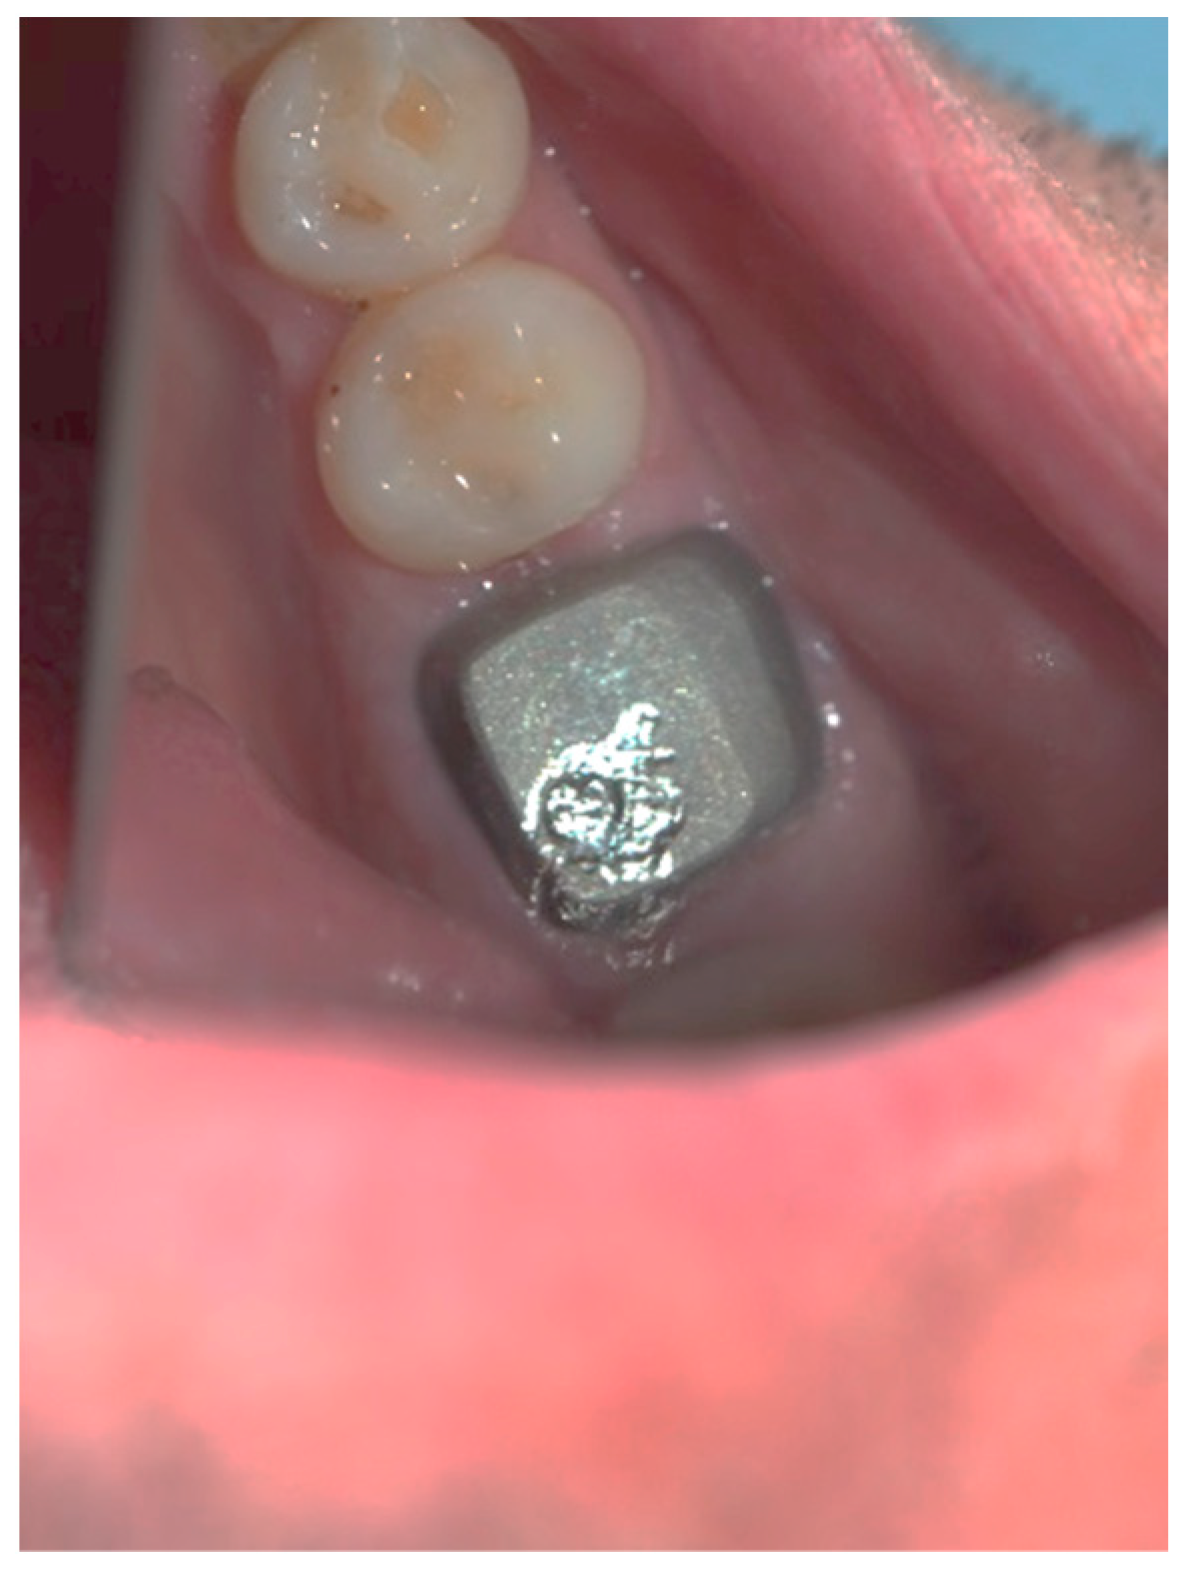

Figure 3, Figure 4, Figure 5, Figure 6, Figure 7 and Figure 8 display the follow-up of the healing process after a resective procedure for lengthening a short clinical crown with a laser.

Figure 8.

The cemented permanent metal–ceramic crown.